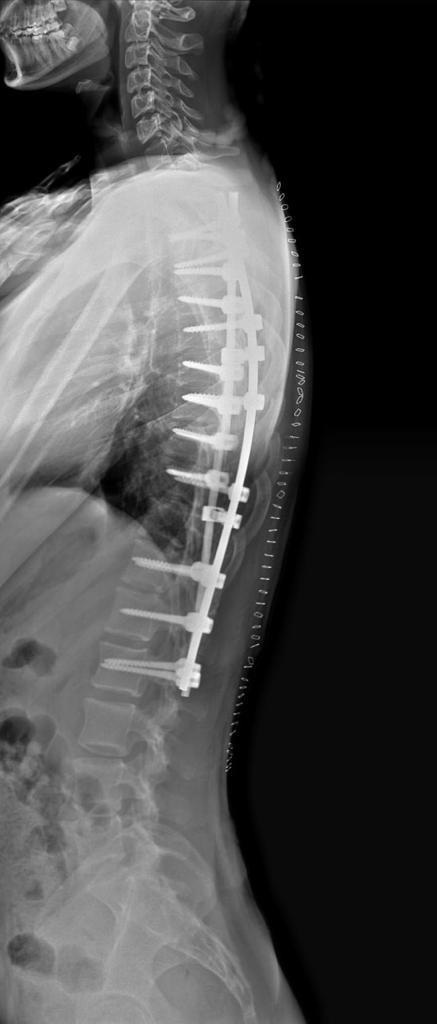

After Surgery